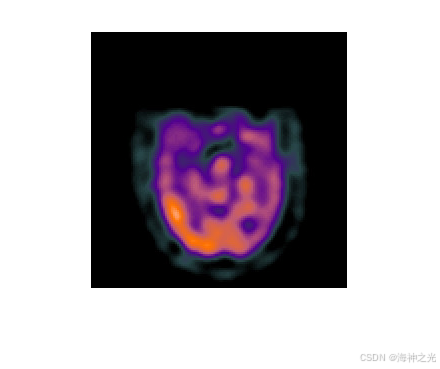

拉普拉斯金字塔(Laplacian Pyramid)是一种多尺度图像表示方法,通过高斯金字塔分解和重建实现。其核心思想是将图像分解为不同频带的子图像,低频部分保留全局结构,高频部分捕捉细节信息。在多模态医学图像融合中,拉普拉斯重分解利用不同模态(如CT、MRI、PET)的互补性,通过频域分离与重组提升融合质量。

- 自适应权重:根据模态特性动态调整低频融合权重(如MRI-T1与PET的代谢信息互补)。

⛄三、运行结果